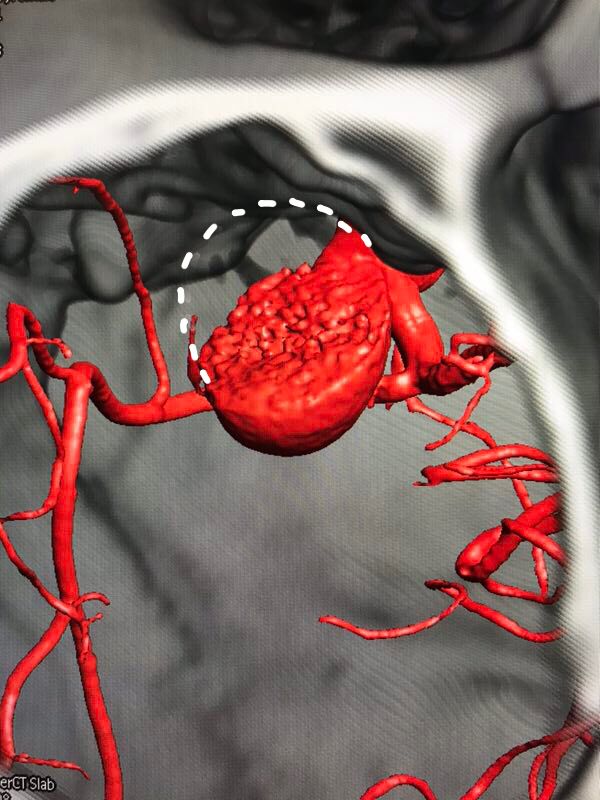

2018.5.8患者全麻下行临时球囊阻断下右侧眼动脉大动脉瘤夹闭术。术中取右侧额外侧入路,形成骨瓣约4*4cm大小,牵开额底,切开蛛网膜释放脑脊液后即见动脉瘤。术中所见瘤体与周边结构解剖关系和术前融合图像完全一致。瘤体表面张力较高,牵开瘤体困难,无法暴露瘤颈和近心端动脉。

术中动脉瘤所见

术前虚拟瘤体大小

结合本病例,我们术前利用复合手术室飞利浦DSA血管机,造影后即刻行CT扫描。由于是在同一机器环境下完成的两种模态扫描,减少了伪影干扰,解剖结构电脑自动吻合,故影像融合精度极高。并且因为是双模态融合,可以用不同颜色标记血管和骨窗,增加了对比度,提高了分辨率,较CTA有明显优势。利用术前融合模拟手术入路,放大后观察发现动脉瘤体巨大,紧贴颅底和床突,缺乏至少2mm的近端阻断空间,术中需要磨除前床突。但术中发现动脉瘤表面张力极高,紧贴床突硬脑膜,高速磨钻操作存在巨大风险。而术中球囊阻断颈内动脉后,动脉瘤张力明显下降,依靠吸引器轻轻牵拉即可暴露出瘤颈,不必要磨除床突,降低了手术复杂度。